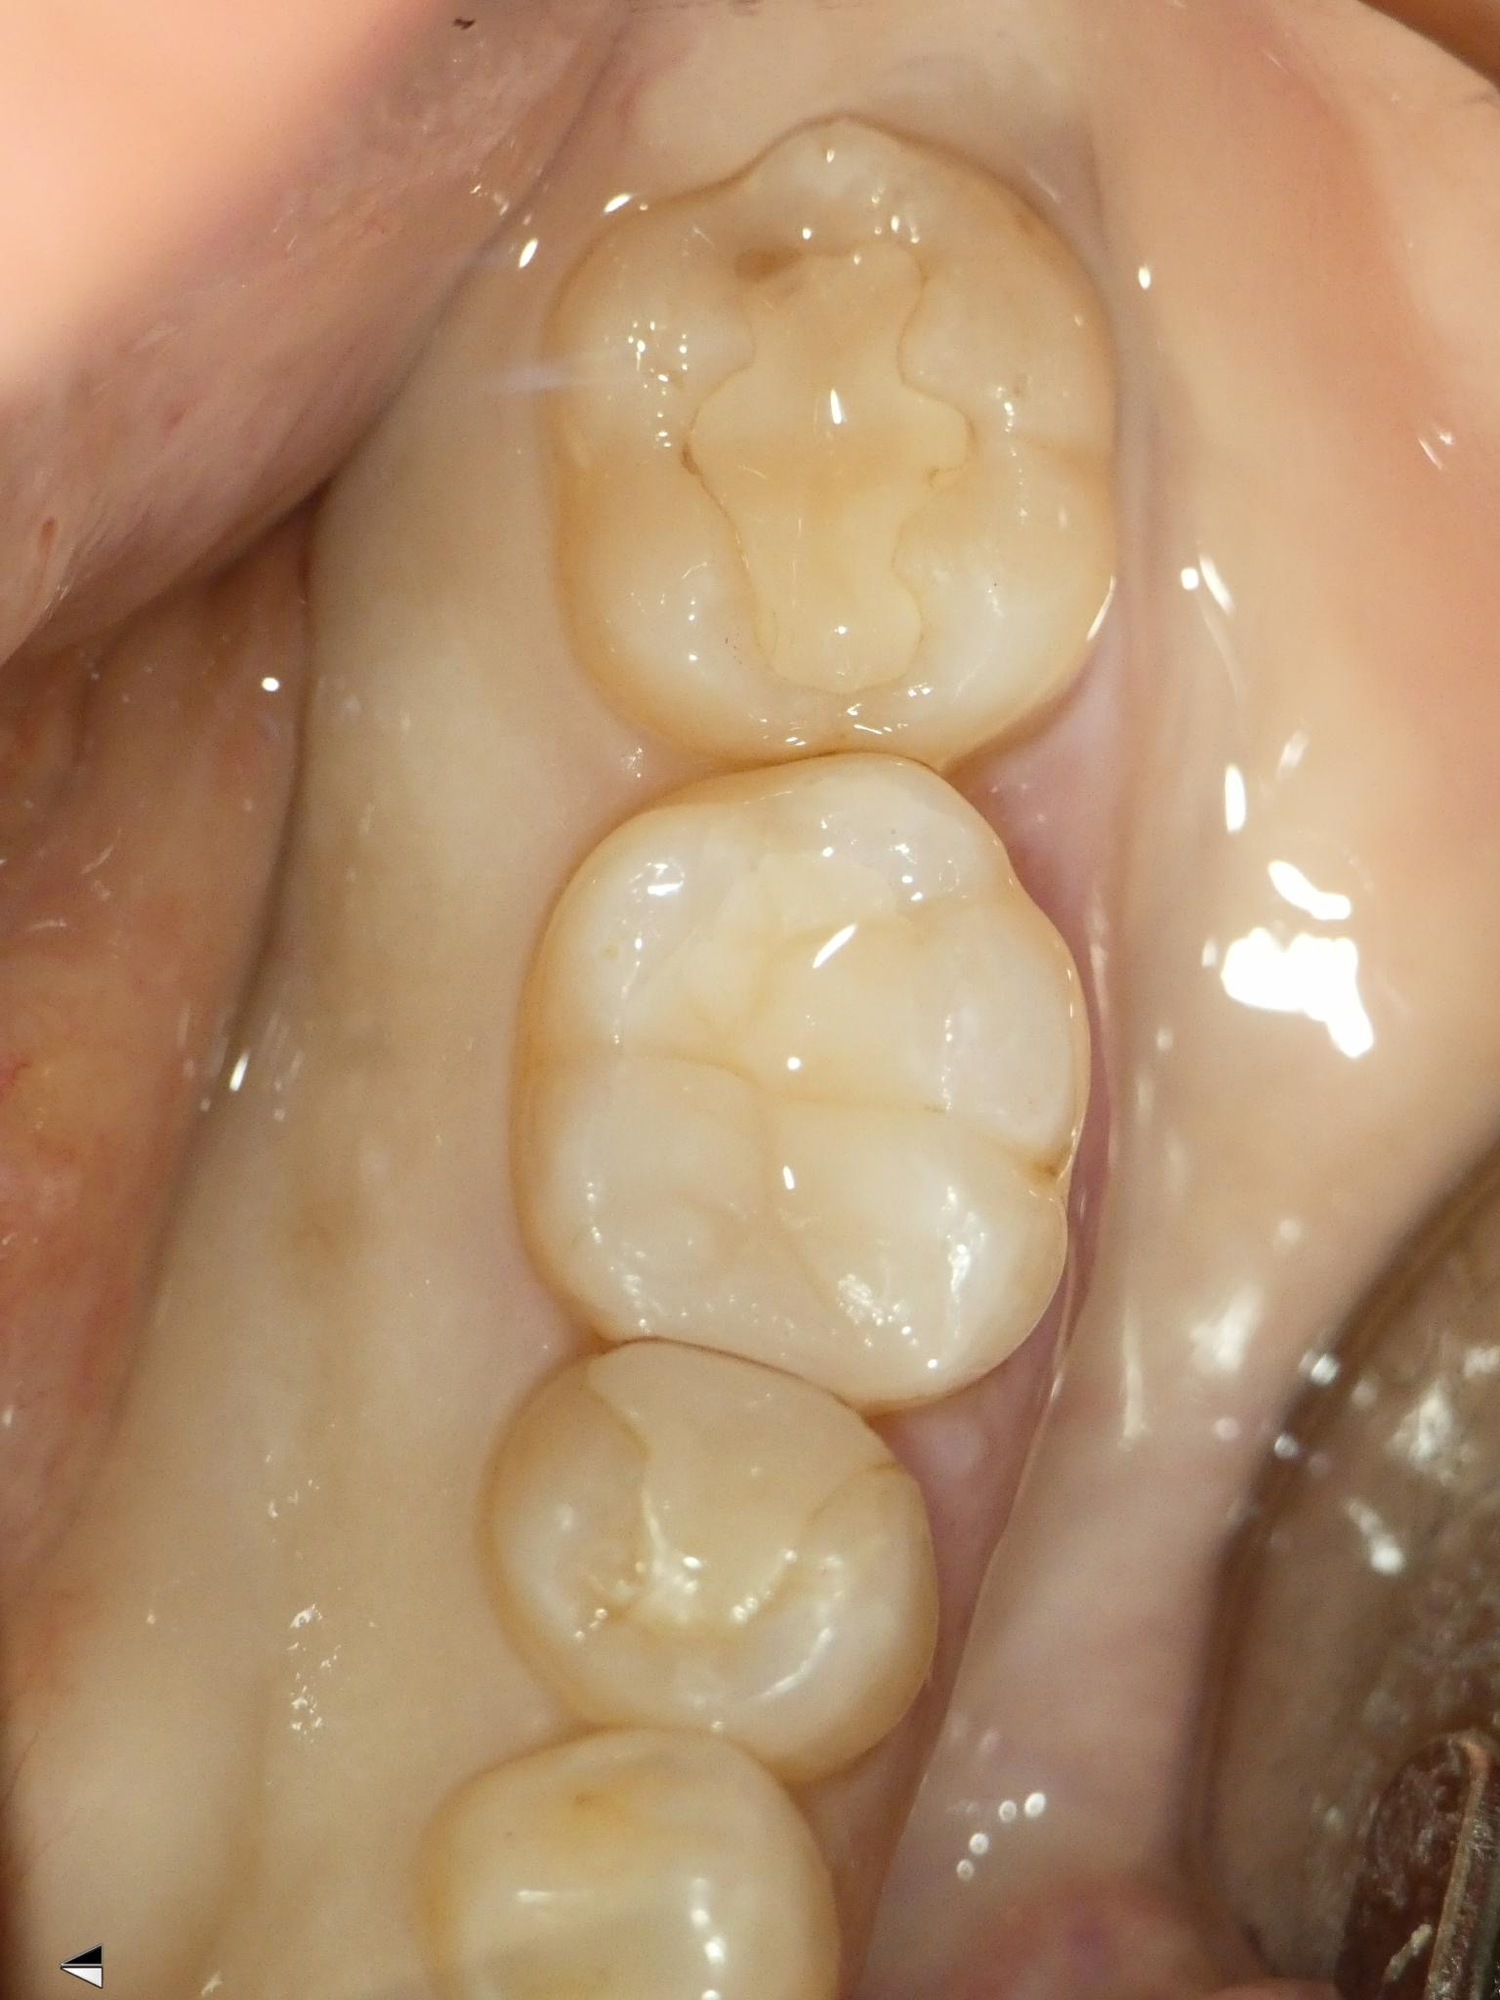

左下の前から6番の歯の虫歯治療の症例を紹介させていただきます。

こちらは保険診療で、コンポジットレジン修復で治療をしております。